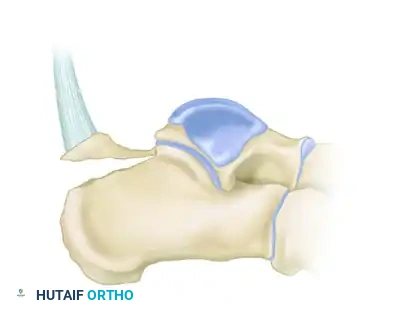

Understanding the morphology of the avulsion is critical for selecting the appropriate fixation strategy. These fractures are generally classified into three distinct types:

Type I: Sleeve Fracture

A thin sliver of cortical bone is avulsed from the posterior tuberosity, often involving the direct insertion of the Achilles tendon.

Type II: Beak Fracture

An oblique fracture exiting dorsally, creating a distinct "beak" fragment. This fragment is highly prone to proximal displacement due to the Achilles tendon.

Type III: Infrabursal Fracture

An avulsion fracture occurring lower on the tuberosity, typically sparing the primary Achilles insertion but involving the retrocalcaneal bursa region.

Below is an example of a severe calcaneal avulsion with a large fragment threatening the posterior envelope: